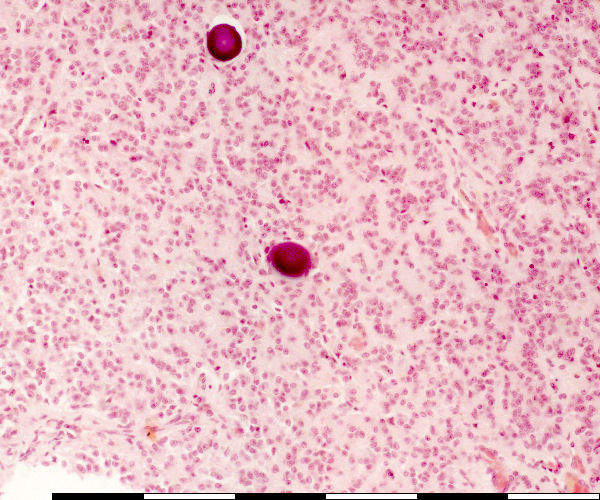

Pineal gland: High magnification